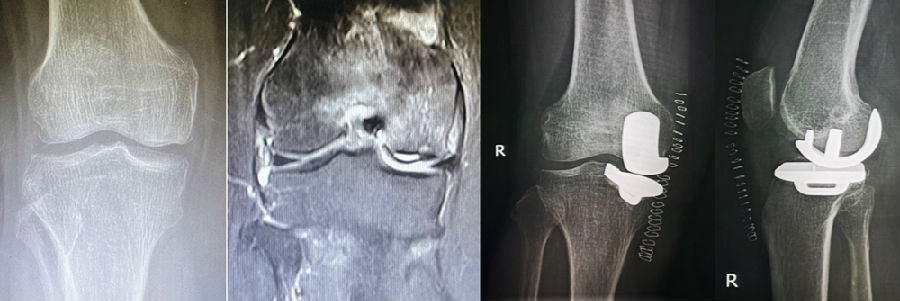

病例1:女,61岁,右膝关节诊断为Koshino Ⅲ期SONK,行右膝内侧单髁手术治疗。

(4)Koshino Ⅳ期SONK

由于存在继发退行性改变,一般不建议单纯行膝关节镜+自体骨软骨移植术。需在考虑5个因素的基础上兼顾患者年龄、性别和活跃程度,分别选择膝关节镜+HTO术+微骨折术、膝关节镜+HTO+坏死区病灶刮除+自体植骨术或单髁置换术。对于合并症状性髌股关节炎、外翻畸形、坏死区范围大影响单髁假体稳定性等的Koshino Ⅳ期膝关节股骨内侧髁SONK,采用全膝关节置换术。

病例1:男,64岁,主诉左膝关节内侧疼痛6年余。MR提示骨坏死区占比为33.28%,矢状位病变区域前后径为26.42mm,半月板相对突出百分比(RPE)31.78%,同时存在胫骨侧来源的下肢内翻畸形(MPTA83°),关节线会聚角2°。

行关节镜检查+软骨摘除+微骨折+HTO术,术后随访2年恢复良好,活动自如,行走时无左膝关节疼痛不适。

病例2:女,81岁,行内侧单髁手术治疗,术后恢复良好。